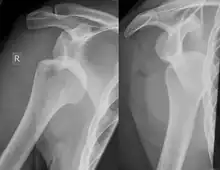

| Anterior shoulder dislocation on X-ray with a large Hill–Sachs lesion | |

A Hill–Sachs lesion, or Hill–Sachs fracture, is a cortical depression in the posterolateral head of the humerus. It results from forceful impaction of the humeral head against the anteroinferior glenoid rim when the shoulder is dislocated anteriorly.

Diagnosis can be suspected by history and physical examination which is usually followed by imaging. Because of the mechanism of injury, apprehension of anterior dislocation is common with provocative maneuvers. Hill–Sachs lesions have been classified as "engaging" or "non-engaging", with engaging lesions defined by the ability of the glenoid to sublux into the humeral head defect during abduction and external rotation. Engaging dislocations have a higher risk of recurrent anterior dislocation, and their presence can help guide surgical management.[2] Imaging diagnosis conventionally begins with plain film radiography. Generally, anteroposterior (AP) radiographs of the shoulder with the arm in internal rotation offer the best yield while axillary views and AP radiographs with external rotation tend to obscure the defect. However, pain and tenderness in the injured joint make appropriate positioning difficult and in a recent study of plain film x-ray for Hill–Sachs lesions, the sensitivity was only about 20%. i.e. the finding was not visible on plain film x-ray about 80% of the time.[3]